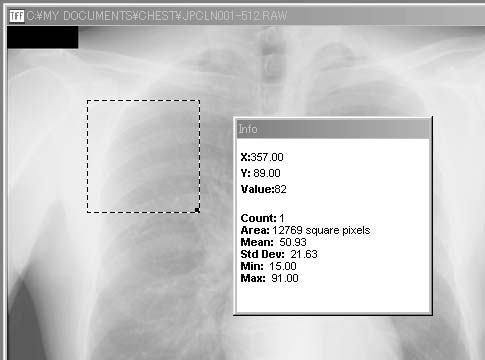

A.. Measure(計測)

「Measure」では,画像の基本的な特徴量をInfoウィンドウに表示する.図5-2の例では,領域選択ツールでChest画像中の点線で囲まれた領域の計測を行った結果である.Infoウィンドウ中に示されるように,画素数による面積(Area:12769 square pixels),画素値の平均(Mean:50.93),標準偏差(Std Dev:21.63),最小値(Min:15.00),および最大値(Max:91.00)が計算されている.特に領域を選択しない場合には,画像全体について計測される.

図5-2 「Measure」による指定領域内(点線内)の基本的な特徴量の表示例